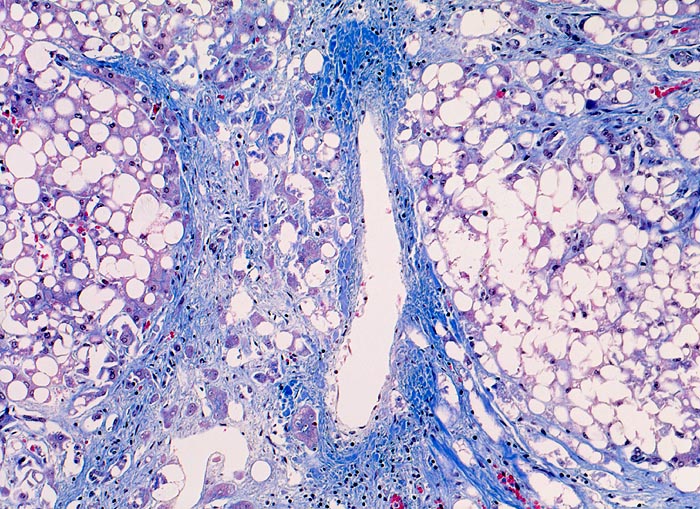

Meist findet sich eine grobtropfige oder gemischttropfige Verfettung des Parenchyms. Schon im Frühstadium der alkoholischen Steatohepatitis kann eine perizelluläre Maschendrahtfibrose, perisinusoidale und perivenuläre Fibrose mit Beginn in der Zone 3 festgestellt werden. Die Kombination von perivenulärer und perizellulärer (> 1096) Fibrose wird bei starker Ausprägung mit Arealen von dichter Kollagenfaserbildung auch als zentrale sklerosierende hyaline Nekrose bezeichnet. Wenn der Vernarbungsprozess fortschreitet, kann die perivenuläre Fibrosezone mit vernarbten Portalfeldern verschmelzen. Zentralvenen verschwinden oder sind stark in der Anzahl reduziert. Eine Phlebosklerose oder Obliteration der Zentralvenen kann hinzukommen. Breite Bänder von fibrotischem Gewebe mit Ductulusproliferationen und gemischtem Entzündungsinfiltrat umgeben die bei alkohlischer Zirrhose meist kleinen Regeneratknoten (=mikronoduläre Leberzirrhose mit Regeneratknoten von weniger als 3mm Durchmesser). Bei längeren Abstinenzphasen kann sich aufgrund der gesteigerten Regeneration auch eine gemischtknotige Zirrhose ausbilden. Ein gleichzeitiges Vorliegen einer Steatose oder Steatohepatitis (Steatose+neutrophile Granulozyten) in einer alkoholischen Leberzirrhose signalisiert in der Regel einen fortgesetzten Aethylabusus. Typisch für alkoholtoxische Leberschädigung sind Mallory-Denk Körperchen (> 3021), Megamitochondrien (> 3022) und eine Zellschwellung (=Ballonierung) aufgrund einer gestörten Albuminausschleusung. Oft können mässige Mengen von Hämosiderinablagerungen vor allem in den Kupffer Zellen nachgewiesen werden. Weitgehend identische morphologische Veränderungen wie bei der aethylischen Leberschädigung finden sich auch bei der nicht alkoholischen Steatohepatitis (NASH) d.h. bei Patienten, die keinen oder nur wenig Alkohol konsumieren.

• Zerstörte Läppchenarchitektur mit diffusem feinknotigem Umbau des Leberparenchyms.

• Breite Fibrosebänder mit Ductulusproliferation und gemischter Entzündung.

• Perivenuläre Fibrose und perizelluläre Maschendrahtfibrose in Zone 3.

• Verminderte Anzahl Zentralvenen.

• Überwiegend makrovesikuläre, teils gemischttropfige Verfettung der Leberzellen.